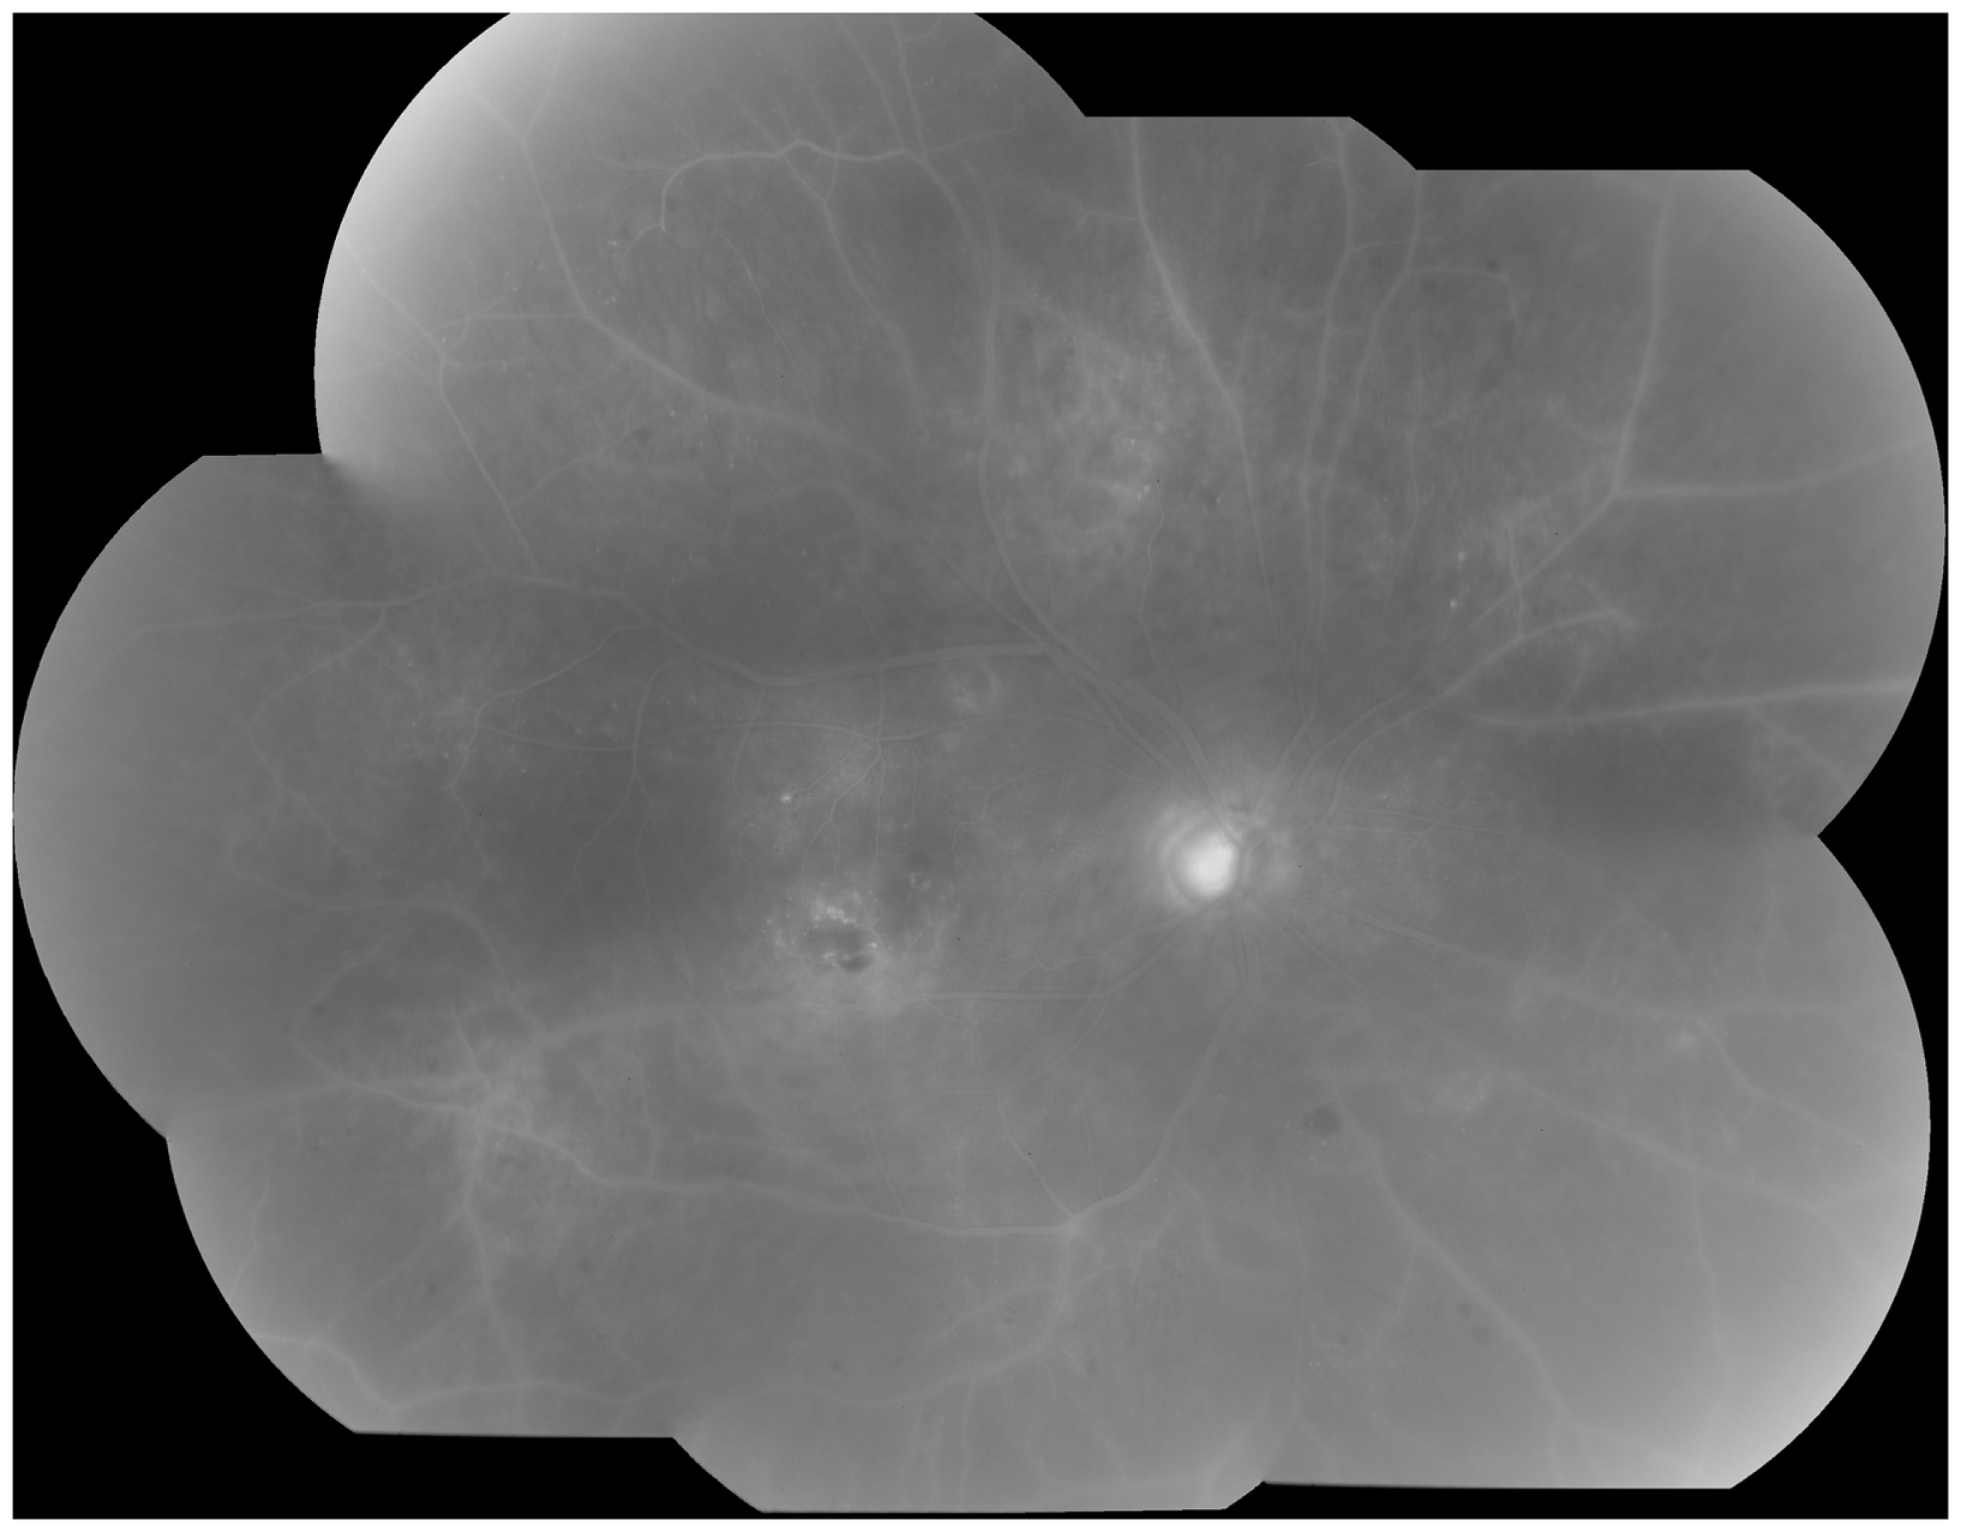

Clinically, retinal ischemia can be adequately identified, and its extension measured, by means of fundus fluorescein angiography (FFA) (Figure 3). For this imaging technique, a dye (fluorescein) is injected in a peripheral vein; images of the fundus are obtained as the dye circulates through the retinal blood vessels. Recently, new emerging technologies using wide-angle fundus cameras have become available (26, 27). These allow obtaining angiograms encompassing a 200-degree field of the retina in a single shot with a nearly complete visualization of the whole retinal vascular tree (Figure 4). Other new imaging techniques are being developed, such as differential phase-contrast swept-source optical coherence tomography (OCT), which allows visualization of retinal blood vessels without the need for injection of dyes (28–30).

Figure 3. Fluorescein angiography obtained from the right eye of a patient with non-proliferative diabetic retinopathy. Note diffuse retinal non-perfusion and ischemia in the midperipheral retina in the absence of neovascularization.

Figure 4. Wide-angle fluorescein angiography obtained with the Optos imaging system. Note excellent visualization of the vascular tree in the posterior pole and midperipheral retina with a single short.